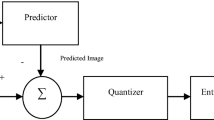

Advanced image scanning techniques produce high resolution medical images such as CT, MRI which in turn needs large storage space and bandwidth for transmitting over a network. Lossless compression is preferred for medical images to preserve important diagnostic details. However, it is only sufficient to maintain the high quality of an image in a diagnostically important region, namely Region of interest (ROI) for an accurate diagnosis. Non -ROI portion when compressed near-losslessly does not affect the image quality but reduces the file size effectively. We propose a compression technique where the prediction is done by Resolution Independent Gradient Edge Detector (RIGED) to de-correlate the image pixels and block-based arithmetic coding is used for encoding. The optimal threshold value, optimal q-level and the block-based coding removes inter-pixel, psycho-visual and coding redundancy from non-ROI part to achieve high compression whereas ROI part is compressed losslessly by removing inter-pixel and coding redundancy only. In this paper, optimal threshold-based predictive lossless compression in the ROI and optimal quantization (q) based near-lossless compression in the rest of the region is proposed. The proposed method is evaluated on volumetric 8 bit and 16 bit standard MR image data-set and validated on real patient’s 16 bit depth MR images collected from local hospitals. The performance of the proposed technique showed improvement over the existing techniques JPEG 2000, JPEG-LS, M-CALIC, JP3D, and CALIC by 40.89%, 34.50%, 32.92%, 22.36%, and 17.25% respectively in terms of Bits per Pixel (BPP).